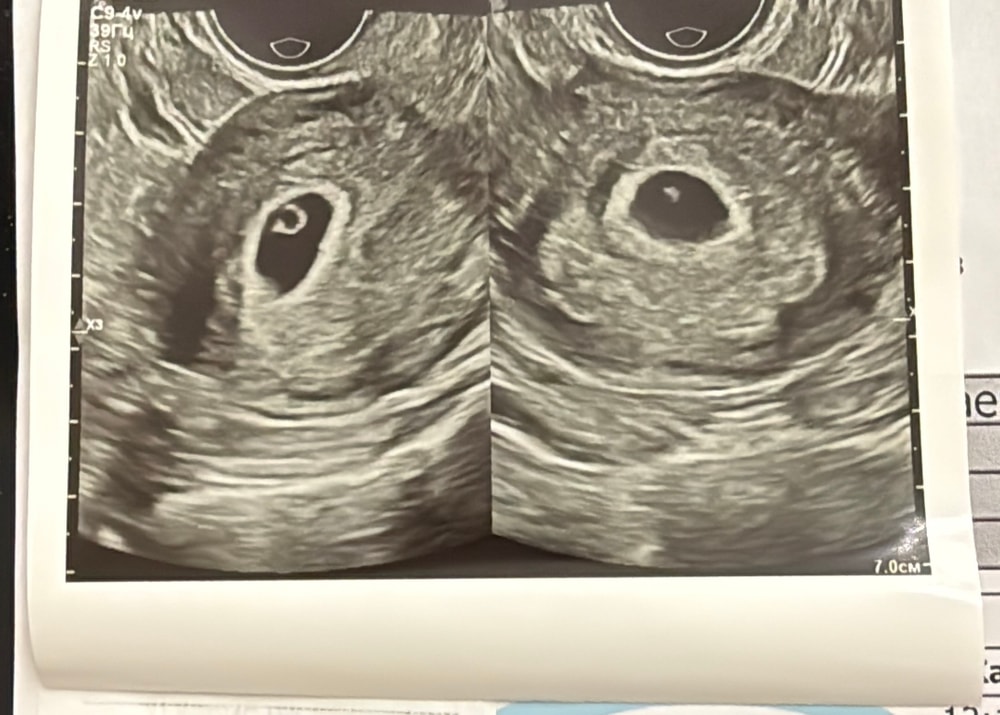

Узи на 23дпп

Результаты УЗИСегодня сходила на Узи, ктр 1.5, плодное яйцо 13мм сердцебиение + Следующее узи хочу на 8 недель сходить. Со старшим бегала каждую неделю. В этот раз не хочу тратить свои нервы на панику.